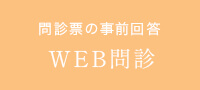

別の日の検診の際の写真です。

やはり残っています。

両方の写真の、かぶせものをご覧ください。

そう、、、プラークの付着が見られないのがお分かりいただけますでしょうか。